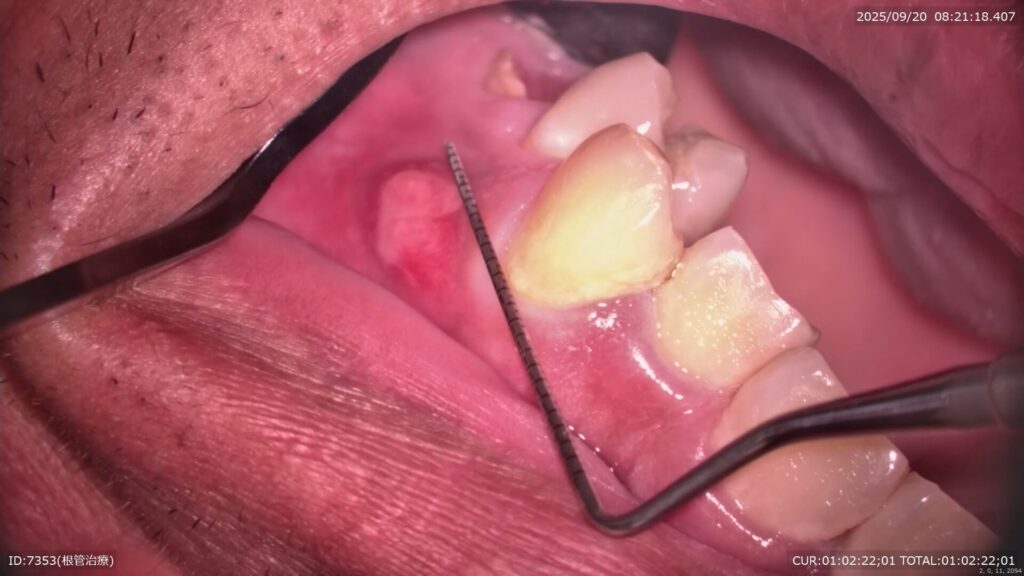

2.初診時の所見

・歯冠部が治療の繰り返しとう蝕によって大きく崩壊(👉治療の繰り返しによるサイクル)

・フェルール(歯ぐきの上の健全歯質)がほぼゼロ

・根尖部に病変/感染の可能性

・このままクラウンを被せても 歯が薄く、破折リスクが極めて高い状態

①根管治療に先立ち、CR(コンポジットレジン)にて隔壁を製作した。

根管治療に入る前に、まず CR(コンポジットレジン)で隔壁 を作りました。 これは見た目を整えるためではなく、根管を細菌から守り、安全に治療を行うための大切なステップです。

②ラバーダム防湿を行い、根管治療→根管充填まで行った。